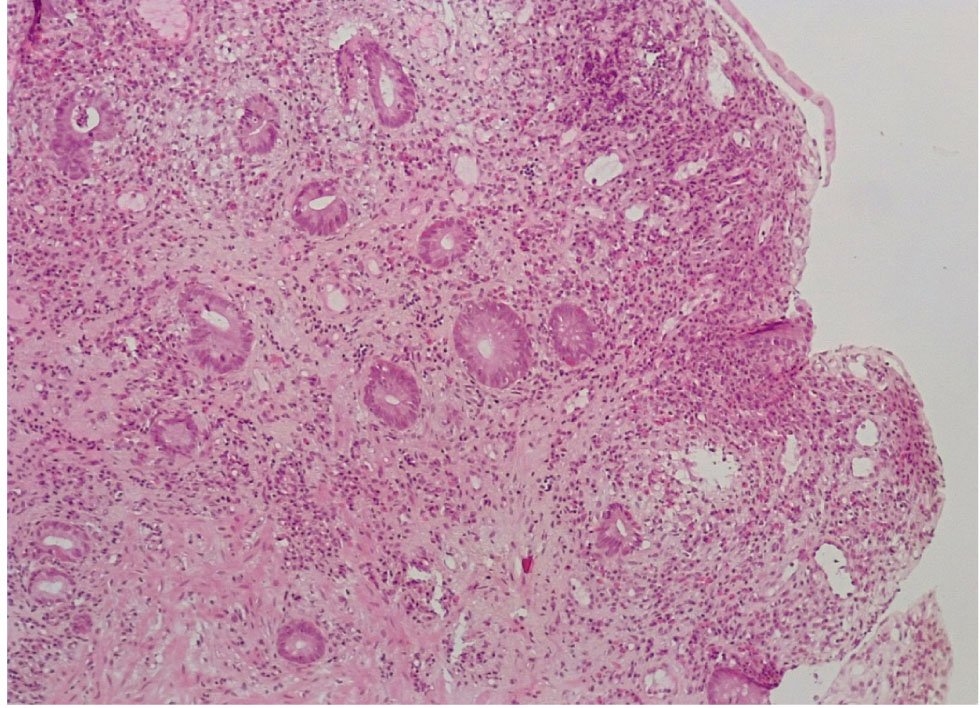

В контрольной группе биопсий слизистой оболочки (СО) толстой кишки, выполненной по поводу хронического поверхностного колита, были обнаружены следующие морфо-гистохимические изменения. СО толстой кишки была сохранена, цилиндрический (столбчатый) эпителий располагался в один слой, содержал на всем протяжении кислые гликопротеиды (ШИК-реакция). Крипты СО на всем протяжении были сформированы правильно, содержали до 12–15 бокаловидных клеток на крипту, содержали альциан+ муцин, что свидетельствовало о наличии в них нейтральных мукополисахаридов (рис. 1, 2).